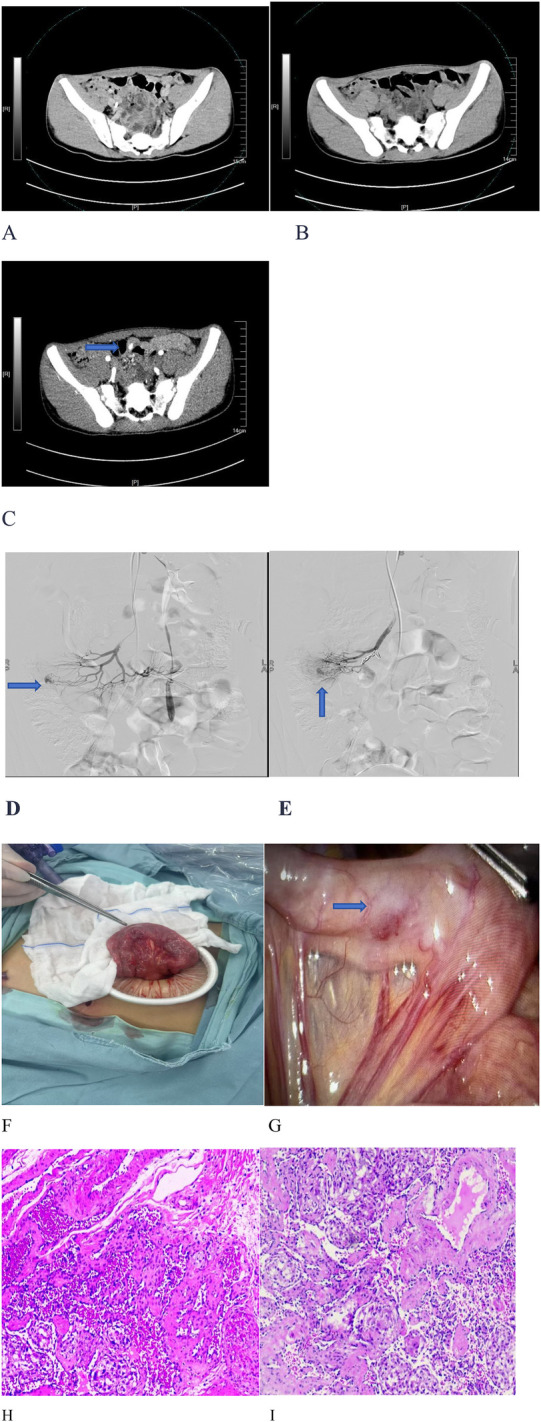

Background: A cavernous hemangioma in the small intestine is rare. Due to its hidden location and non-specific clinical symptoms, it is difficult to diagnose accurately. Here, we describe a 14-year-old boy with a cavernous hemangioma and bleeding at the junction of the jejunum and ileum.

Case summary: The patient presented with clinical manifestations including melena, dizziness, fatigue, pale complexion, and shock. Abdominal contrast-enhanced computed tomography identified a hyperdense lesion within the small bowel lumen. Digital subtraction angiography (DSA) revealed aneurysmal changes in the mid-to-lower abdominal branches of the ileojejunal artery, which were suggestive of a hemorrhage originating from a small intestinal hemangioma. However, subsequent DSA-guided interventional embolization failed to achieve hemostasis. Following a hospital-wide multidisciplinary consultation, a laparoscopic exploration was conducted. During the procedure, a 1.5 cm × 1.5 cm mass was detected at the ileojejunal junction and successfully resected. The postoperative pathological examination confirmed the lesion to be a cavernous hemangioma. One week after surgery, the patient's hemoglobin level increased to 86 g/L, with no recurrence of bloody stools. At the 1-month follow-up, no signs of disease recurrence were observed.

Conclusion: This case report presents significant clinical implications for the diagnosis and management of small intestinal cavernous hemangiomas in the pediatric population.